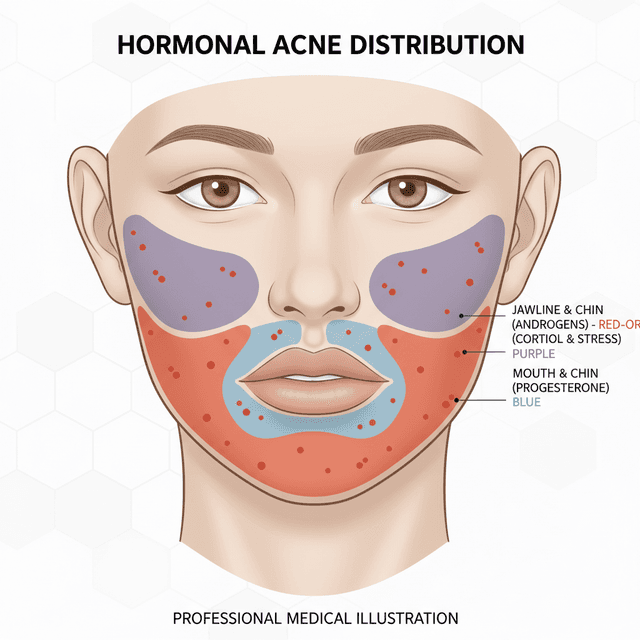

Hormonal Acne Patterns: How to Identify Hormone-Driven Breakouts by Location and Timing

Where your acne appears on your face can reveal what's causing it. Learn to read your breakout patterns — jawline, chin, cheeks — and understand what your hormones are telling you.